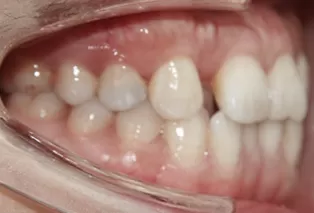

Photos intra-orales